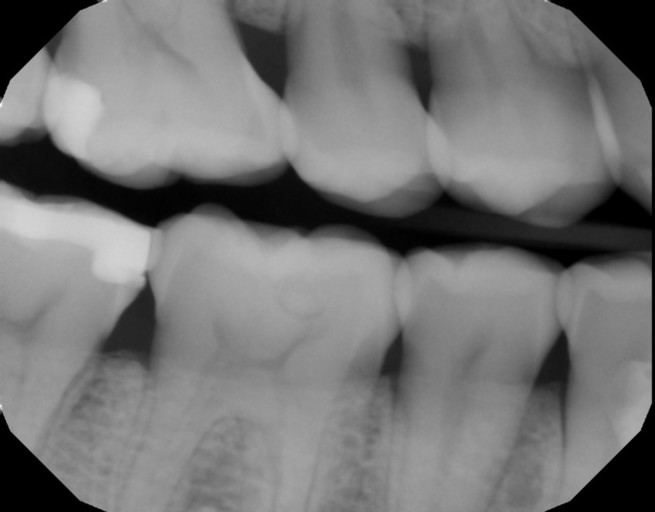

Almost-brodie bite with SFOT. Looking for provider recommendations

I went to my original orthodontist really wanting a wider smile and a fix to my overbite {content removed} sleep apnea. He proposed removing two premolars in order to prepare for double jaw surgery. I had the two lower premolars removed in addition...